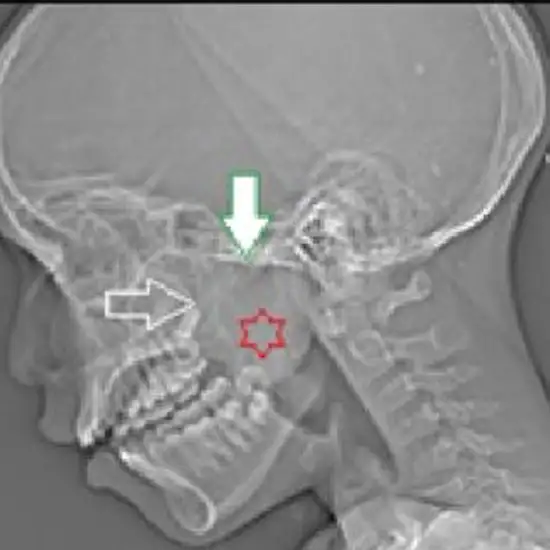

NCCT Nasopharynx is a Non-Contrast Computed Tomography of the Nasopharynx. It is a diagnostic imaging scan that is used to obtain cross-sectional images of the nasopharynx, air-filled hollow sinuses, and pharynx. Doctors recommend this scan to identify the pharynx and larynx inflammation and also to diagnose the root cause of sore throat and nasal obstruction.

Doctors usually recommend this scan to diagnose and determine the inflammation of the sinus, pharynx, and larynx, the sore throat, nasal obstruction and its causes, and nasopharynx abnormalities such as cancer, bone fractures, genetic malfunction, etc.

The NCCT in NCCT Nasopharynx stands for Non-contrast computed tomography, this is an imaging technique that is also known as a plain study of the Nasopharynx region. It is used to visualize the associated pathology and the internal structures for any disease conditions in the Nasopharynx region.